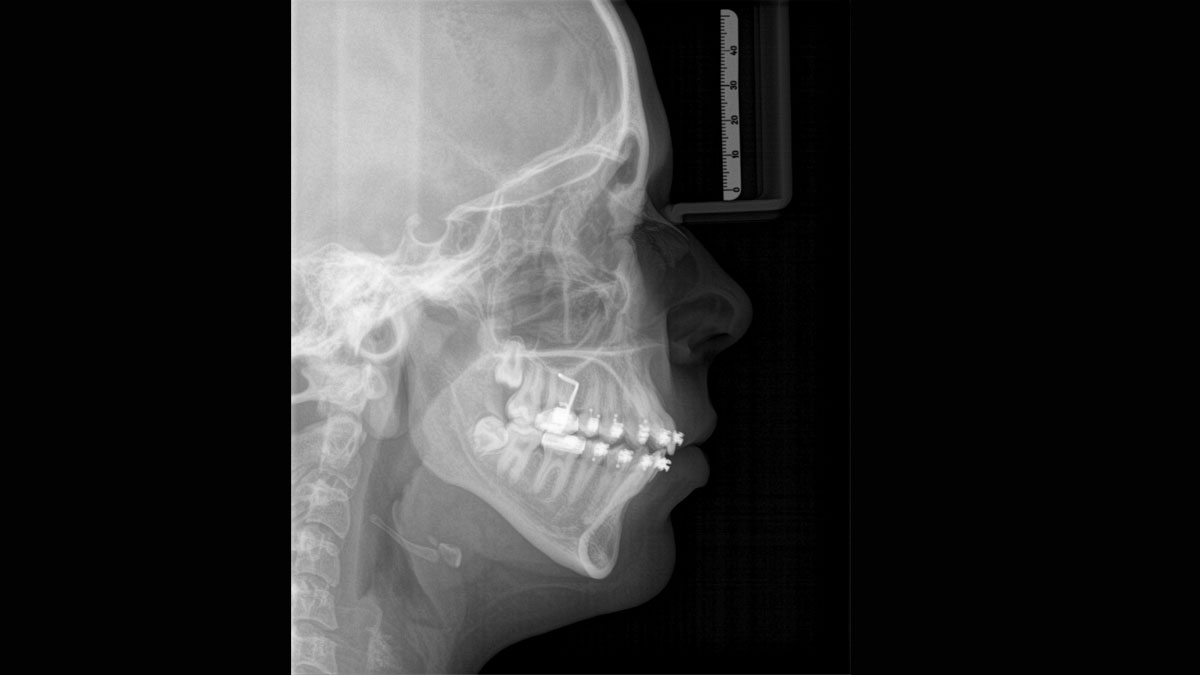

For exceptional panoramic images with high sharpness. You can choose an optional right or left cephalometric arm, which can be retrofitted at any time